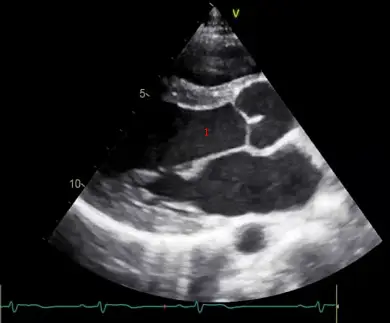

下圖為心臟超音波胸骨旁長軸( PLAX )影像,標號 1 的解剖部位應為:

本題考查心臟超音波(Echocardiography)中最基礎且重要的切面:胸骨旁長軸切面(Parasternal Long Axis view, PLAX) 的解剖構造識別。在進行心臟超音波檢查時,PLAX 通常是第一個獲取的切面,用來評估左心室大小、收縮功能、心室中膈與後壁厚度,以及二尖瓣與主動脈瓣的形態與活動狀況。

觀察提供的 PLAX 影像,探頭置於胸骨左緣,超音波音束由前胸壁向心臟後方掃描。我們可以依序辨認出以下解剖構造:

- 最上方(靠近探頭處)的無回音區:右心室(Right Ventricle, RV)。在 PLAX 切面中,右心室位於最前方。

- 分隔上下兩個心室的帶狀高回音構造:心室中膈(Interventricular Septum, IVS)。

- 影像中央最大的無回音腔室(標號 1 所在位置):左心室(Left Ventricle, LV)。

- 標號 1 下方(後方)的肌肉壁:左心室後壁(Left Ventricular Posterior Wall, LVPW)。

- 影像右下側的腔室:左心房(Left Atrium, LA)。

- 左心房與左心室之間的瓣膜:二尖瓣(Mitral Valve, MV)。